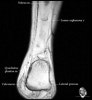

- Axial section

Axial PD fat suppression evaluates the tendons and ligaments of the ankle particularly after acute/subacute injuries. It also is sensitive to talar dome osteochondral defects. Alternatively, a T2 sequence can be used to eliminate magic angle artifact that may occur as the tendons travel around the malleolar turns.

Tibiofibular ligaments

Lateral ankle ligaments

Deltoid and spling ligaments

Tendon(Achilles, Medial, Lateral, Anterior)